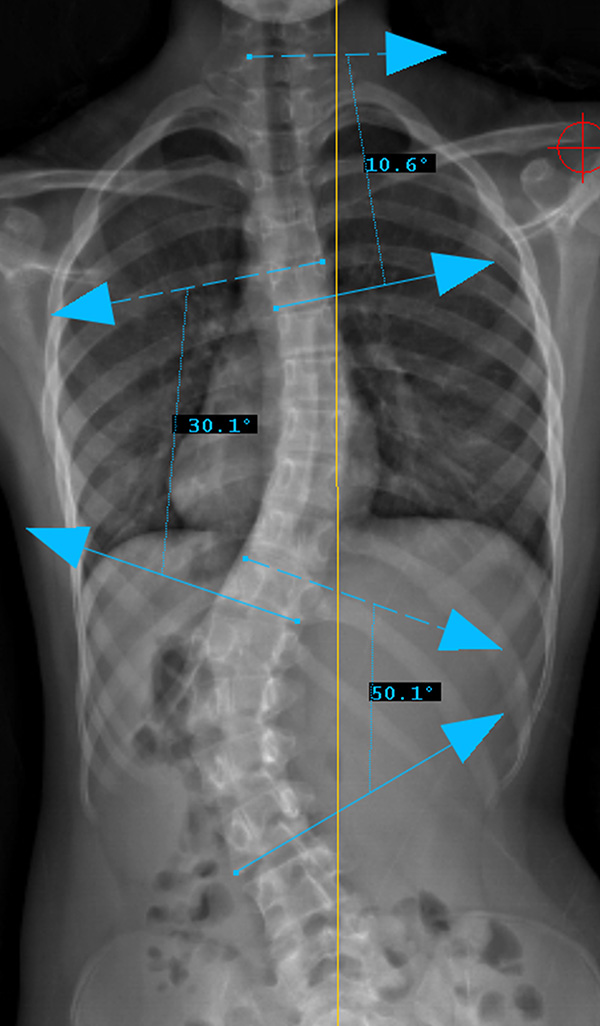

Preop PA View

Curve Type 5

Lumbar curve major, other curves non-structural.

Lumbar modifier C

CSVL does not touch apex of lumbar curve

(apex - L1/2 disc)

Therefore, Classification is Type 5CN

Lenke Type V describes a major curve in the thoracolumbar/lumbar region. The apex of the greatest coronal plane deformity is between T12 and L4. The main thoracic curve is non-structural with a side-bending Cobb of less than 25 degrees and a T10-L2 kyphosis of less than 20 degrees. All of these curves have a “C” lumbar spine modifier. The three sagittal modifiers are still applicable. These curves may be treated with either an anterior or posterior spinal fusion. The fusion levels are often the upper and lower end-vertebrae of the coronal plane deformity. For successful selective fusion of the thoracolumbar/lumbar spine the Cobb angle, apical vertebral translation, and apical vertebral rotation ratios (ThL/L:MT) should be greater than 1.25. In addition the MT curve should be flexible without evidence of thoracolumbar junctional kyphosis (T10-L2 > 20 degrees).